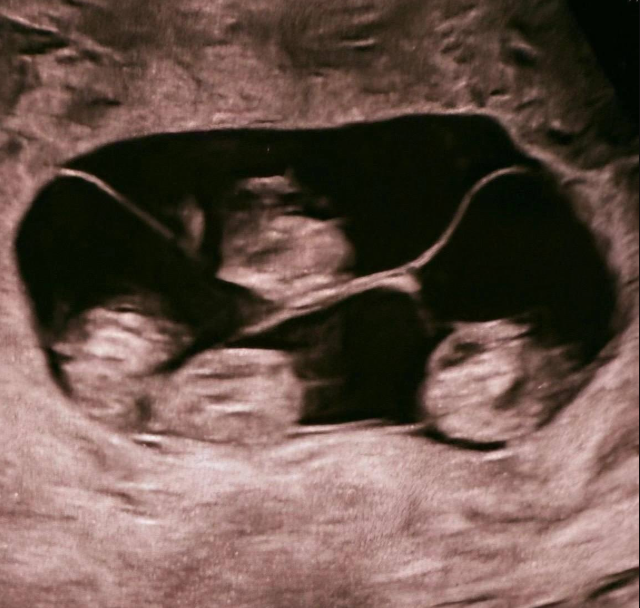

В Санкт-Петербурге произошёл редчайший случай для России — женщина родила однояйцевых четверняшек. Вероятность такого события оценивается примерно как 1 на 15,5 миллиона родов.

На свет появились четыре абсолютно идентичные девочки, сейчас за ними наблюдают врачи. Подобные случаи — настоящая редкость: во всём мире зафиксировано около 15 таких рождений, и чаще всего это именно девочки.